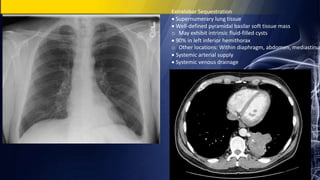

Extralobar Sequestration

 Supernumerary lung tissue

 Well-defined pyramidal basilar soft tissue mass

o May exhibit intrinsic fluid-filled cysts

 90% in left inferior hemithorax

o Other locations: Within diaphragm, abdomen, mediastinum

 Systemic arterial supply

 Systemic venous drainage

Extralobar Sequestration  Supernumerarylung tissue  Well-defined pyramidal basilar soft tissue mass o May exhibit intrinsic fluid-filled cysts  90% in left inferior hemithorax o Other locations: Within diaphragm, abdomen, mediastinum  Systemic arterial supply  Systemic venous drainage